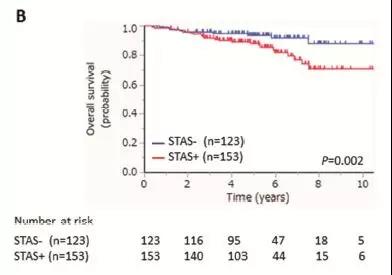

图表B:STAS阳性(91.3%)比STAS阴性(98.3%)病人术后5年肺癌相关的总体生存率明显降低